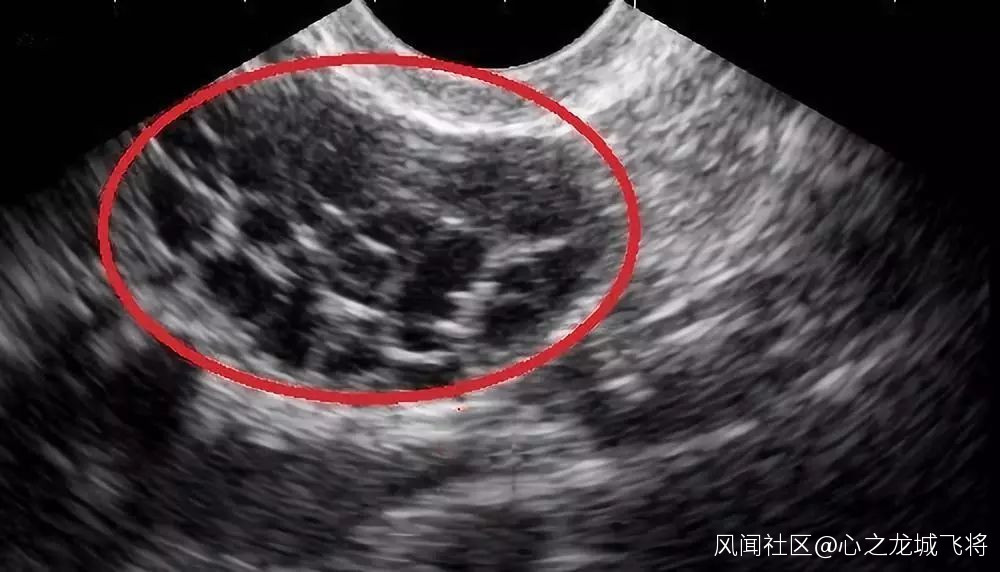

<超聲波下顯示的卵巢過度刺激綜合症>

捐卵者需要經過至少兩週的荷爾蒙刺激,然後才能動手術取出卵子。注射荷爾蒙所引發的併發症不但痛苦萬分,且可能危及性命。